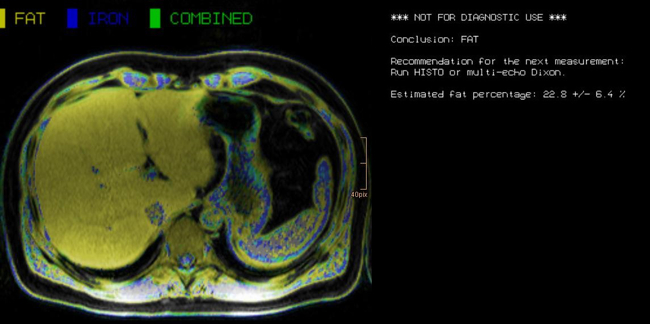

Morphological and functional MRI in all-organ systems development of novel MRI applications and MR sequences. Examples of research projects: fat, iron or combined disease; influence of iron on the evaluation of liver fat.

a) MRI for the evaluation of diffuse liver disease:

evaluation of different MRI methods (relaxometry, chemical shift imaging, multi-echo approach, Dixon screening), in order to detect diffuse liver disease (fat, iron or combined disease); influence of iron on the evaluation of liver fat.